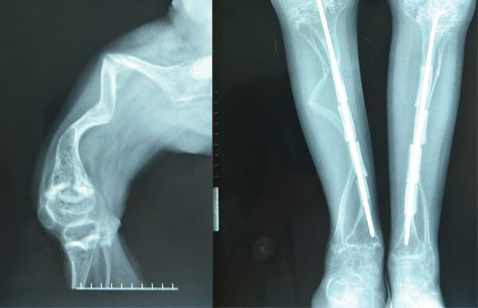

Viêm tủy xương

Viêm tủy xương là một nhiễm khuẩn xương, có thể đột ngột và cấp tính nhưng cũng có thể là mạn tính.Các triệu chứng bao gồm đau xương cục bộ, căng tức, đỏ và sưng phù, có thể sốt và ớn lạnh. Cách điều trị có thể là dùng kháng sinh và trong một số trường hợp có thể phẫu thuật để loại bỏ các mô xương bị viêm nhiễm.